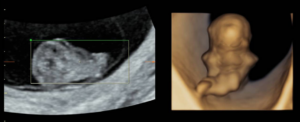

The ultrasound images demonstrated a single spinal column, two stomachs, and two hearts (Figure 2A). Two fused abdomens were observed, along with subcutaneous edema measuring 2.0 mm and 2.1 mm (Figure 2B). In addition, two pairs of moving legs were identified (Figure 2C). The trophoblast was located anteriorly, and a single corpus luteum was observed in the left ovary. Two follow-up examinations were required at 9 and 10 weeks of gestation to establish the diagnosis. At 9 weeks of gestation, the 3D ultrasound images lacked sufficient clarity for a definitive diagnosis (Figure 3). At 10 weeks of gestation, color Doppler imaging demonstrated two distinct cardiac activities, indicating the presence of two separate circulatory systems (Figure 4A). Three-dimensional imaging further revealed the face of one of the conjoined twins and confirmed the presence of two umbilical cords (Figure 4B).